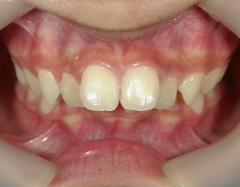

矯正歯科 治療後矯正歯科 全顎ワイヤー矯正 治療後矯正歯科(全顎ワイヤー矯正)治療後

矯正歯科 治療後

no.18_2196_治療後_右.jpgno.18_2196_治療後_正面.jpgno.18_2196_治療後_左.jpg